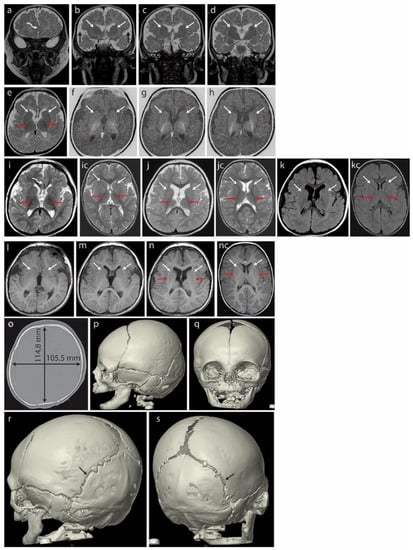

Magnetic resonance imaging (MRI) of the brain at 3 months (Figure 2a–h) revealed hypoplasia/fenestration of the anterior falx cerebri with the gyri of the right cerebral hemisphere crossing the brain midline (Figure 2a—curved arrow), as well as incomplete opercularization (Figure 2b—black arrows).

Brain MRI of the patient at 3 months (a–h) revealed hypoplasia/fenestration of the anterior falx cerebri with the gyri of the right cerebral hemisphere crossing the midline ((a)—curved arrow) and incomplete opercularization, which is normally complete at term ((b)—black arrows). Roundish basal ganglia in the coronal plane in T2-weighted images (T2WI) ((b–d)—white arrows). At this age, the posterior limbs of the internal capsules (PLICs—red arrows) are well myelinated: black in T2WI ((e)—axial plane) and white in the inversion recovery (IR) sequence, best depicting the myelinated structures (f–h). There is no trace of even the unmyelinated lines separating the caudate and lentiform nuclei that would represent the anterior limbs of the internal capsules (ALICs) ((b–h)—white arrows). A further brain MRI scan at 18 months (i–n) did not detect the ALICs which are normally appreciable at 10–11 months. The basal ganglia appear to be fused bilaterally in both hemispheres ((j–n) white arrows in the axial plane: (j)—T2WI, (k)—FLAIR, (l–n)—T1WI); opercularization remained incomplete (i). Normal PLICs ((i)—red arrows). (ic) Corresponding sections in the normal brain of an 18-month-old boy, T2WI. PLICs—red arrows; normal ALICs separating the caudate and lentiform nuclei—white arrows. (jc) Corresponding sections in the normal brain of an 18-month-old boy, T2WI. PLICs—red arrows; normal ALICs separating the caudate and lentiform nuclei—white arrows. (kc) Corresponding sections in the normal brain of an 18-month-old boy, FLAIR. PLICs—red arrows; normal ALICs separating the caudate and lentiform nuclei—white arrows. (nc) Corresponding sections in the normal brain of an 18-month-old boy, T1WI. PLICs—red arrows; normal ALICs separating the caudate and lentiform nuclei—white arrows. Computed tomography (CT) of the skull at age 4 months (o–s) showed a brachycephalic skull (the cephalic index of 91.9 exceeded the range of 76 to 81 compatible with a mesaticephalic skull in normal males). Asymmetric lambdoid suture: narrower on the left (r—black arrow) compared with the wider right one (s—black arrow).

Unusually rounded basal ganglia are visible in the coronal plane in T2-weighted images (T2WI) (Figure 2b–d, white arrows). The posterior limbs of the internal capsules (PLICs, red arrows) are well myelinated: these structures appear black in T2WI on the axial plane (Figure 2e) and white in inversion recovery (IR) sequences highlighting the myelinated structures (Figure 2f–h). The anatomical line normally separating the caudate and lentiform nuclei from the anterior limbs of the internal capsules (ALICs) remains undetectable at the structural and myelination levels (Figure 2b–h, white arrows), indicating severely disrupted/delayed myelination. This is currently considered rare in B-WS patients [8].

A brain MRI at 18 months (Figure 2i–n) showed that opercularization remained incomplete (Figure 2i, red arrows). The anterior limbs of the internal capsules (ALICs) that are normally appreciable at 10–11 months were not detected. The basal ganglia appear to be fused bilaterally (Figure 2j–n, arrows showing fusion lines).

A CT of the skull at age 4 months (Figure 2o–q) showed a brachycephalic skull with a cephalic index of 91.9, indicating pathologically disturbed proportions of the skull. This exceeded the range of 76 to 81 compatible with a mesaticephalic skull in normal males. A SD greater than 3.5 between the length and width of the skull was noted at 33 months (−2.29 SD vs. 1.32 SD). We note that the initial physical examination suggested positional brachycephaly with a discrete asymmetry of the occiput (plagiocephaly), but a later CT examination ruled out positional skull deformation because there were clear differences in the width of the lambdoid suture: it was narrow on the left side and wide on the right (Figure 2r,s).